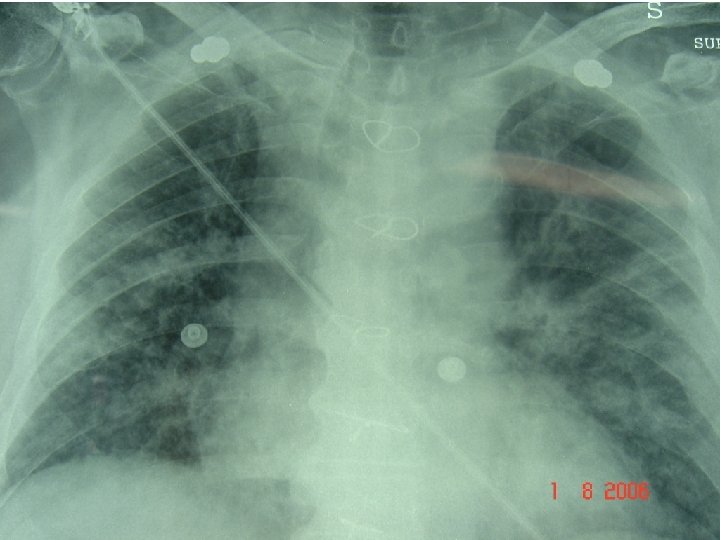

I. R. A. ALI ARDS Insorgenza acuta Infiltrati polmonari bilaterali non segni di ipertensione polmonare ( WP < 18 mm. Hg ) Pa. O 2/Fi. O 2 < 300 Pa. O 2/Fi. O 2 < 200 Indipendentemente dalla PEEP

Talamini et Al. Serum creatinine and chest radiographs in the early assessment of acute pancreatitis. Am J Surg. 1999 Jan; 177(1): 7 -14. L’aumento della creatininemia e la presenza di versamento pleurico e/o addensamento parenchimale polmonare permette di identificare un sottogruppo di ptz a rischio di evoluzione più grave o di decesso.